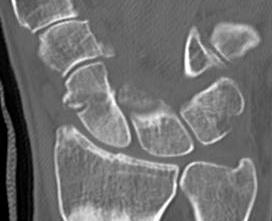

CT

Indication: any potential displacement

Position: patient prone with fully pronated hand over head

Instability

- displacement > 1mm on any film

- intra-scaphoid angle > 35o

- comminution

- proximal pole fractures

- perilunate trans-scaphoid dislocation

Scaphoid waist fracture 1 mm displaced

Scaphoid fracture with significant displacement

Scaphoid proximal pole fracture